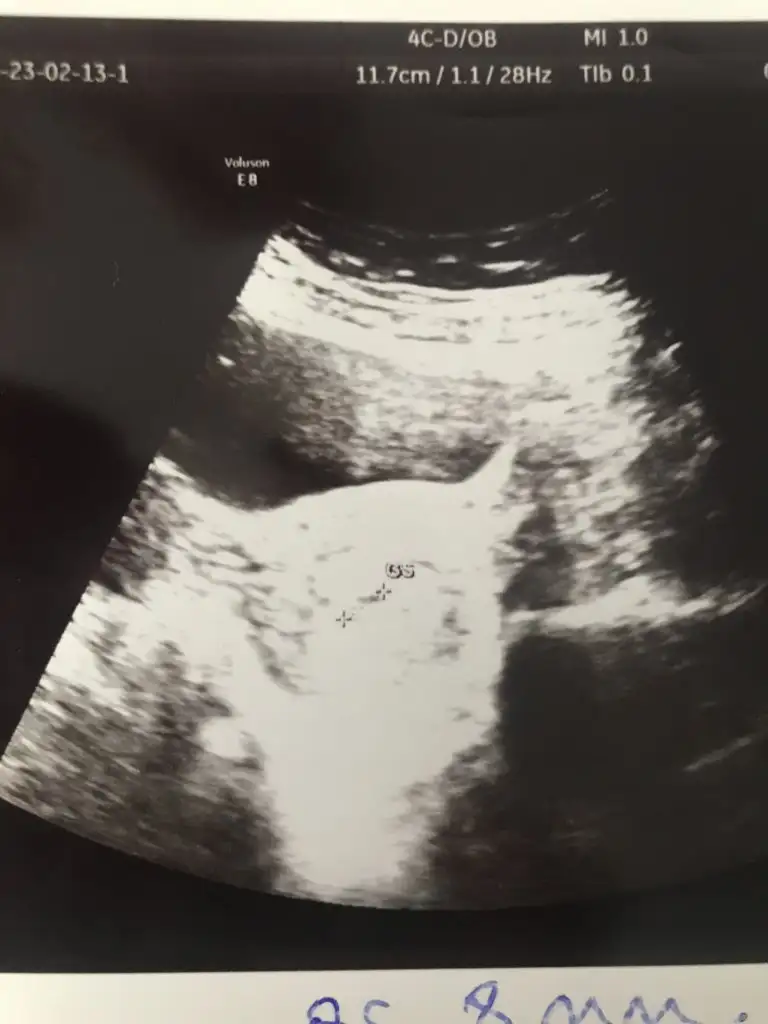

Hayırlısı olsun canım Allah kucağımıza almayı nasip etsin.kağıtta yazıyor canım gs yazıyor.

Kızlar ben de sat’a göre 5+2’yim ve bugün keseyi 8mm olarak gördük çok şükür, rahim ve yumurtalıklar temiz, dış gebelik değil dedi doktor. 2 haftaya kalp atışı kesin duyulur, o zaman gelebilirsin dedi :) rabbim hepimize sağlıklı süreçler versin inşallah 🤲🏻